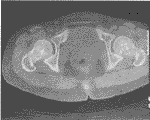

患者男,30岁,体检时发现。查体:无阳性体征。实验室检查:血钙、血磷均正常。X线及CT所见(图1、2):双侧髂骨、髋臼、股骨头及颈部骨松质内见大小不一、圆形及类圆形致密影、边界清晰、直径约0.3~2cm不等。诊断:骨斑点症。

图1